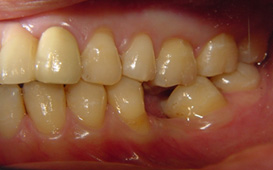

咬合崩塌 / 上牙下墜 / 下牙上長 / 前牙飆出 / 傾倒 / 蛀牙 / 牙周病缺牙未重建 - 臨床實例

上面的牙往下墜,下面的牙往上長,前面的牙往外飆 – 咬合崩塌牙周病,蛀牙;這些現象必然發生,時間越久,問題越大,而且除非藉由矯正及其他牙科治療,無法修正。

缺牙導致牙齒移位 - 臨床實例二